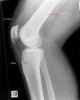

Knee Recognition

Lior Shamir publishes:

- (2009 Jan) Biometric

identification using knee X-rays, Int. J. of Biometrics,

vol. 1, no. 3, pp. 365-370. Inderscience, 2009

Experimental results show that the rank-10 identification accuracy using a dataset of 425 individuals is ~56%, and the rank-1 accuracy is ~34%. - (2013 Jan) MRI-based knee image for personal identification, Int. J. Biometrics, Vol. 5, No. 2, pp.113–125

Knee MRI images of 2,686 different patients were used in the experiment, and analysed using the wndchrm image classification scheme. Experimental results show that the rank-10 identification accuracy using the MRI knee images is ~93% for a dataset of 100 individuals, and ~45% for the entire dataset of 2,686 persons.